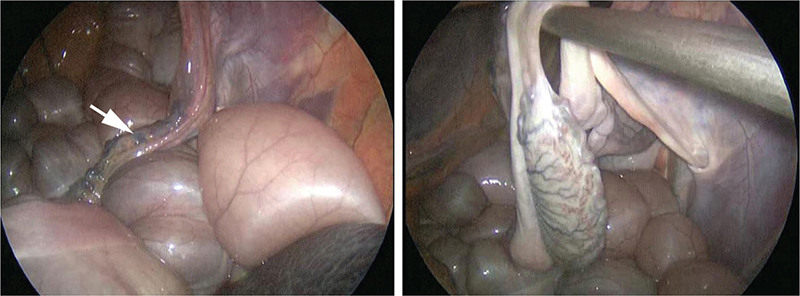

A retained testis may be located anywhere along the course of normal testicular descent. For classification, 3 locations are described: complete abdominal cryptorchidism when the testis and epididymis are located entirely within the abdomen (Figure 4); partial abdominal cryptorchidism when the testis is in the abdomen and the epididymis in the inguinal canal (Figure 5); inguinal cryptorchidism when the testis and epididymis are located within the inguinal canal or adjacent to the external inguinal ring within the inguinal fascia (Figure 6).

Fig. 4.

Figure 4. Laparoscopic view of a complete abdominal testis. The spermatic cord of the retained testis is indicated by the arrow.

Fig. 5.

Figure 5. Laparoscopic view of a partial abdominal testis.

Fig. 6.

Figure 6. Laparoscopic view of an inguinal testis.